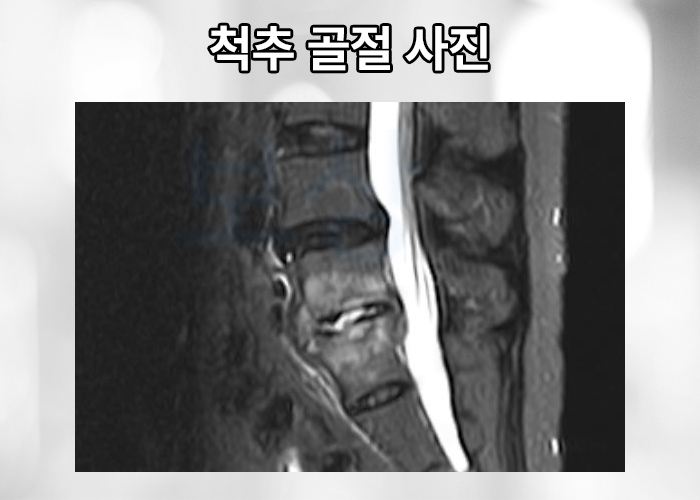

위 mri 촬영한 사진을 보시면 유독 위 아래의 추체와 다르게 눌려있는 척추체가 보이는데요, 위 사진은 요추 5번 압박골절 진단받은 의뢰인의 영상 사진입니다. 의뢰인은 다행히 골절의 정도와 형태가 심하지 않아 TLSO 허리 보조기 착용하며 일정 기간 요양하는 비수술적 보존 치료 시행하게 되었습니다.

하지만 시간이 경과 하며 골밀도가 안 좋은 경우엔 골절된 척추체가 점점 무너져 척추의 전만, 후만의 기형을 야기하게 됩니다. 척추 압박골절로 일정 기간이 지나 괜찮아졌다고 해도 본래 척추 만곡에 기형이 발생할 수 있기 때문에 실비, 입원비, 골절 진단금 뿐만 아니라 후유장해 보상도 알아보아야 합니다.